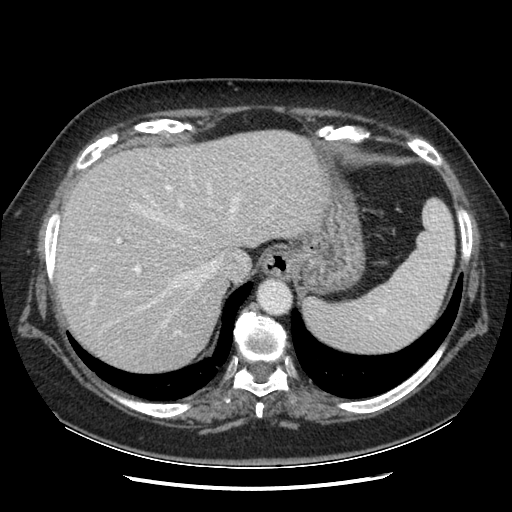

Generated VENOUS CT scan (A→B translation)

Full window (WL 1023.5, WW 4095 → Low −1024, High +3071)

Actual HU range: [-783.9, 601.6]